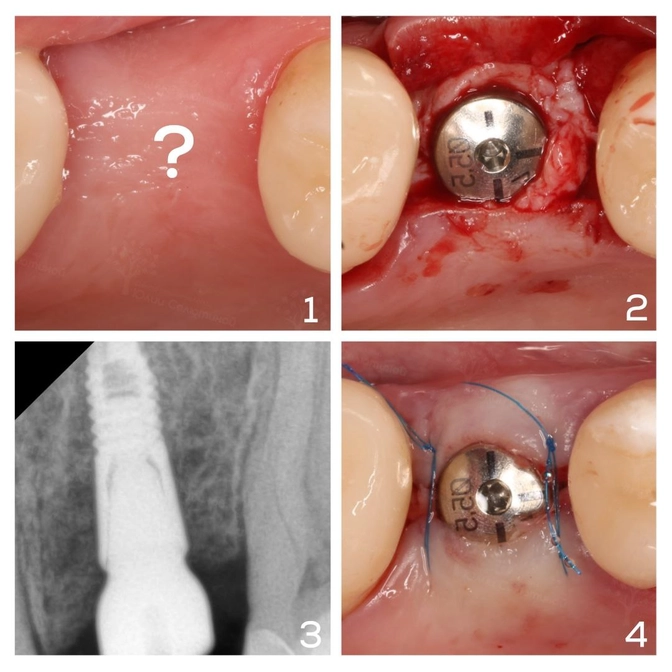

«Шестерка» на верхней челюсти давно утрачена.

Десна в зоне имплантации объемом не радовала.

Стоматолог-хирург решил сделать ход конем и одномоментно провел сразу три этапа:

✔️ вкрутил имплант,

✔️ провел пластику мягких тканей (подсаживал специальный материал, который позволяет достичь нужного объема десны),

✔️ установил формирователь десны, чтобы ткани обрастали сразу по форме будущей коронки.

Такой подход позволяет сократить количество визитов в клинику и уменьшить срок лечения.

После приживления пациентке остается лишь посетить стоматолога-ортопеда для изготовления коронки на имплант.